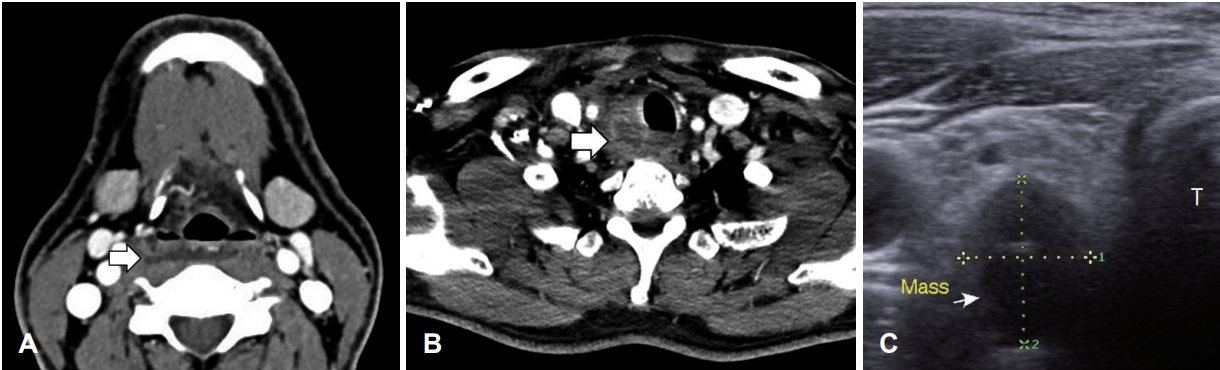

49세 남자 환자가 3일 전부터 시작된 인후통, 발열 등으로 타 병원을 방문하였으며, 목 초음파 검사에서 우측 후인두 부위의 심경부 감염이 의심되어 본원으로 내원하였다. 과거력 상 당뇨 이외에는 특이 소견 없었고, 외상이나 최근 치과 질환의 병력도 없었다. 신체 검사에서는 우측 쇄골 윗부분에 압통을 호소하였으며, 인·후두 내시경 검사상 편도나 후두에 부종이나 발적 등의 소견은 없었다. 혈액 검사상 백혈구 12.46(×103/μL, 3~9.3), 분엽 호중구 79.5(%, 40~70), 적혈구침강속도 7 2(mm/hr, 0 ~30), C-반응단백 10.07(mg/dL, 0~0.5)로 염증 소견이 보였다. 경부 컴퓨터단층촬영에서 윤상연골 높이부터 흉골 상부까지 후인두 공간이 두꺼워져 있었으며 저밀도 음영을 보이고 있는 연조직염 소견이 보였다(Fig. 1A). 우측 갑상선 아래 부분에 1.3×2.1 cm 크기의 농양강(abscess cavity)이 기관 우측 옆에서 후인두 공간까지 침범하고 있었다(Fig. 1B). 초음파에서 우측 갑상선 아래 부분에 저음영의 균질한 1.5×2 cm 크기의 구형 종괴가 관찰되었다(Fig. 1C). 임상 소견들을 바탕으로 후인두 공간 심경부 감염을 먼저 의심하였고, 감별 질환으로 새열 낭종이나 갑상선 또는 부갑상선 기원의 종물에 염증이 합병된 경우 등을 고려하였다. 원인 질환에 대한 탐색적인 관점으로 농양에 대한 응급 절개 및 배농 수술을 계획하였다.